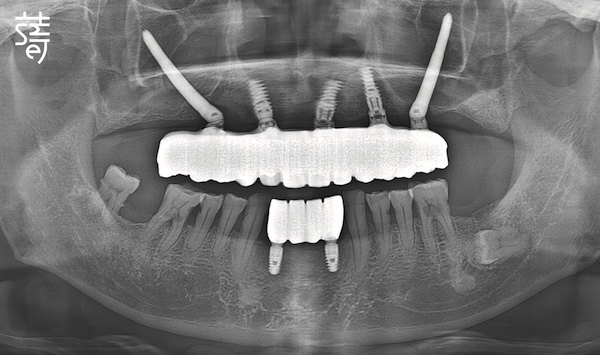

不同於一般診所僅拍攝局部影像,蒔美採用高階全頭顱 CT 掃描,

完整呈現從頭頂到下巴的顏面立體結構,確保醫師能精準避開所有風險區域。

這次重建,上顎 All-on-5採用享譽全球、臨床表現卓越的諾保科Nobel Biocare植體,下顎缺牙部位則選用精密穩定、以創新聞名的士卓曼Straumann植體。

Smile Dental Group used Nobel Biocare implants—renowned worldwide for clinical excellence—for the upper jaw, and Straumann implants—celebrated for precision and durability—for the lower.